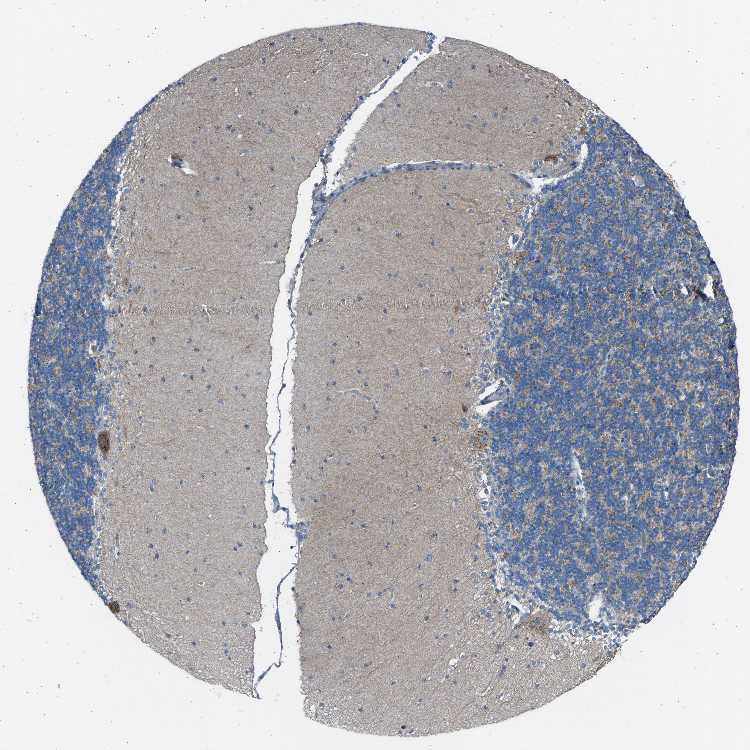

CEREBELLUM - Antibody stainingi

Antibody staining in the annotated cell types in the current human tissue is reported as not detected, low, medium, or high, based on conventional immunohistochemistry profiling in selected tissues. This score is based on the combination of the staining intensity and fraction of stained cells.

Each image is clickable and will lead to virtual microscopy that enables deeper exploration of all samples and also displays staining intensity scores, fraction scores and subcellular localization as well as patient and tissue information for each sample.

Antibody HPA020060

Purkinje cells Medium

Cells in granular layer Medium

Cells in molecular layer Medium